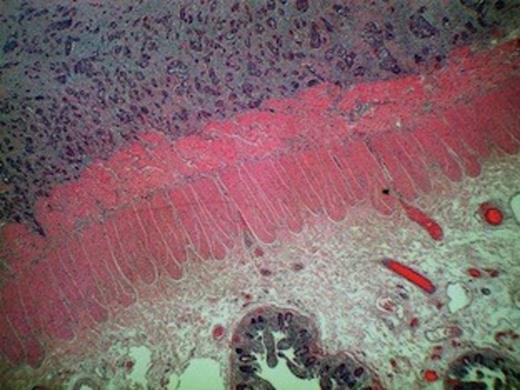

Squamous cell carcinoma metastasis infiltrating peritoneal fat and serosa evident of right hemicolectomy specimen

Despite an initial response to treatment, four months later, the patient presented with clinical picture suggestive of large bowel obstruction. An explorative laparotomy unveiled a large mass involving the terminal ileum and caecum along with dense adhesions of ileocaecal loops. A 4 cm nodule in the right lobe of liver was also discovered. The patient underwent right hemicolectomy with an end-to-end ileocolic anastomosis. The surgical specimen consisted of 21 and 15 cm length of small and large bowel, respectively. The central 10 cm of the bowel was of undeterminable nature due to its tortuous nature caused by innumerable adhesions. The mucosa was unremarkable except for focal oedema. Histological examination showed poorly-differentiated squamous cell carcinoma infiltrating serosa with prominent intravascular spread. The tumour was predominantly confined to the peritoneal fat and serosa with no obvious invasion of the muscularis, submucosal, and mucosal layers (Figure 1 and 2). The appearance was consistent with metastatic spread from primary anal lesion. Unfortunately, the patient did not recover and died from multiple organ failure on the fourth post-operative day.